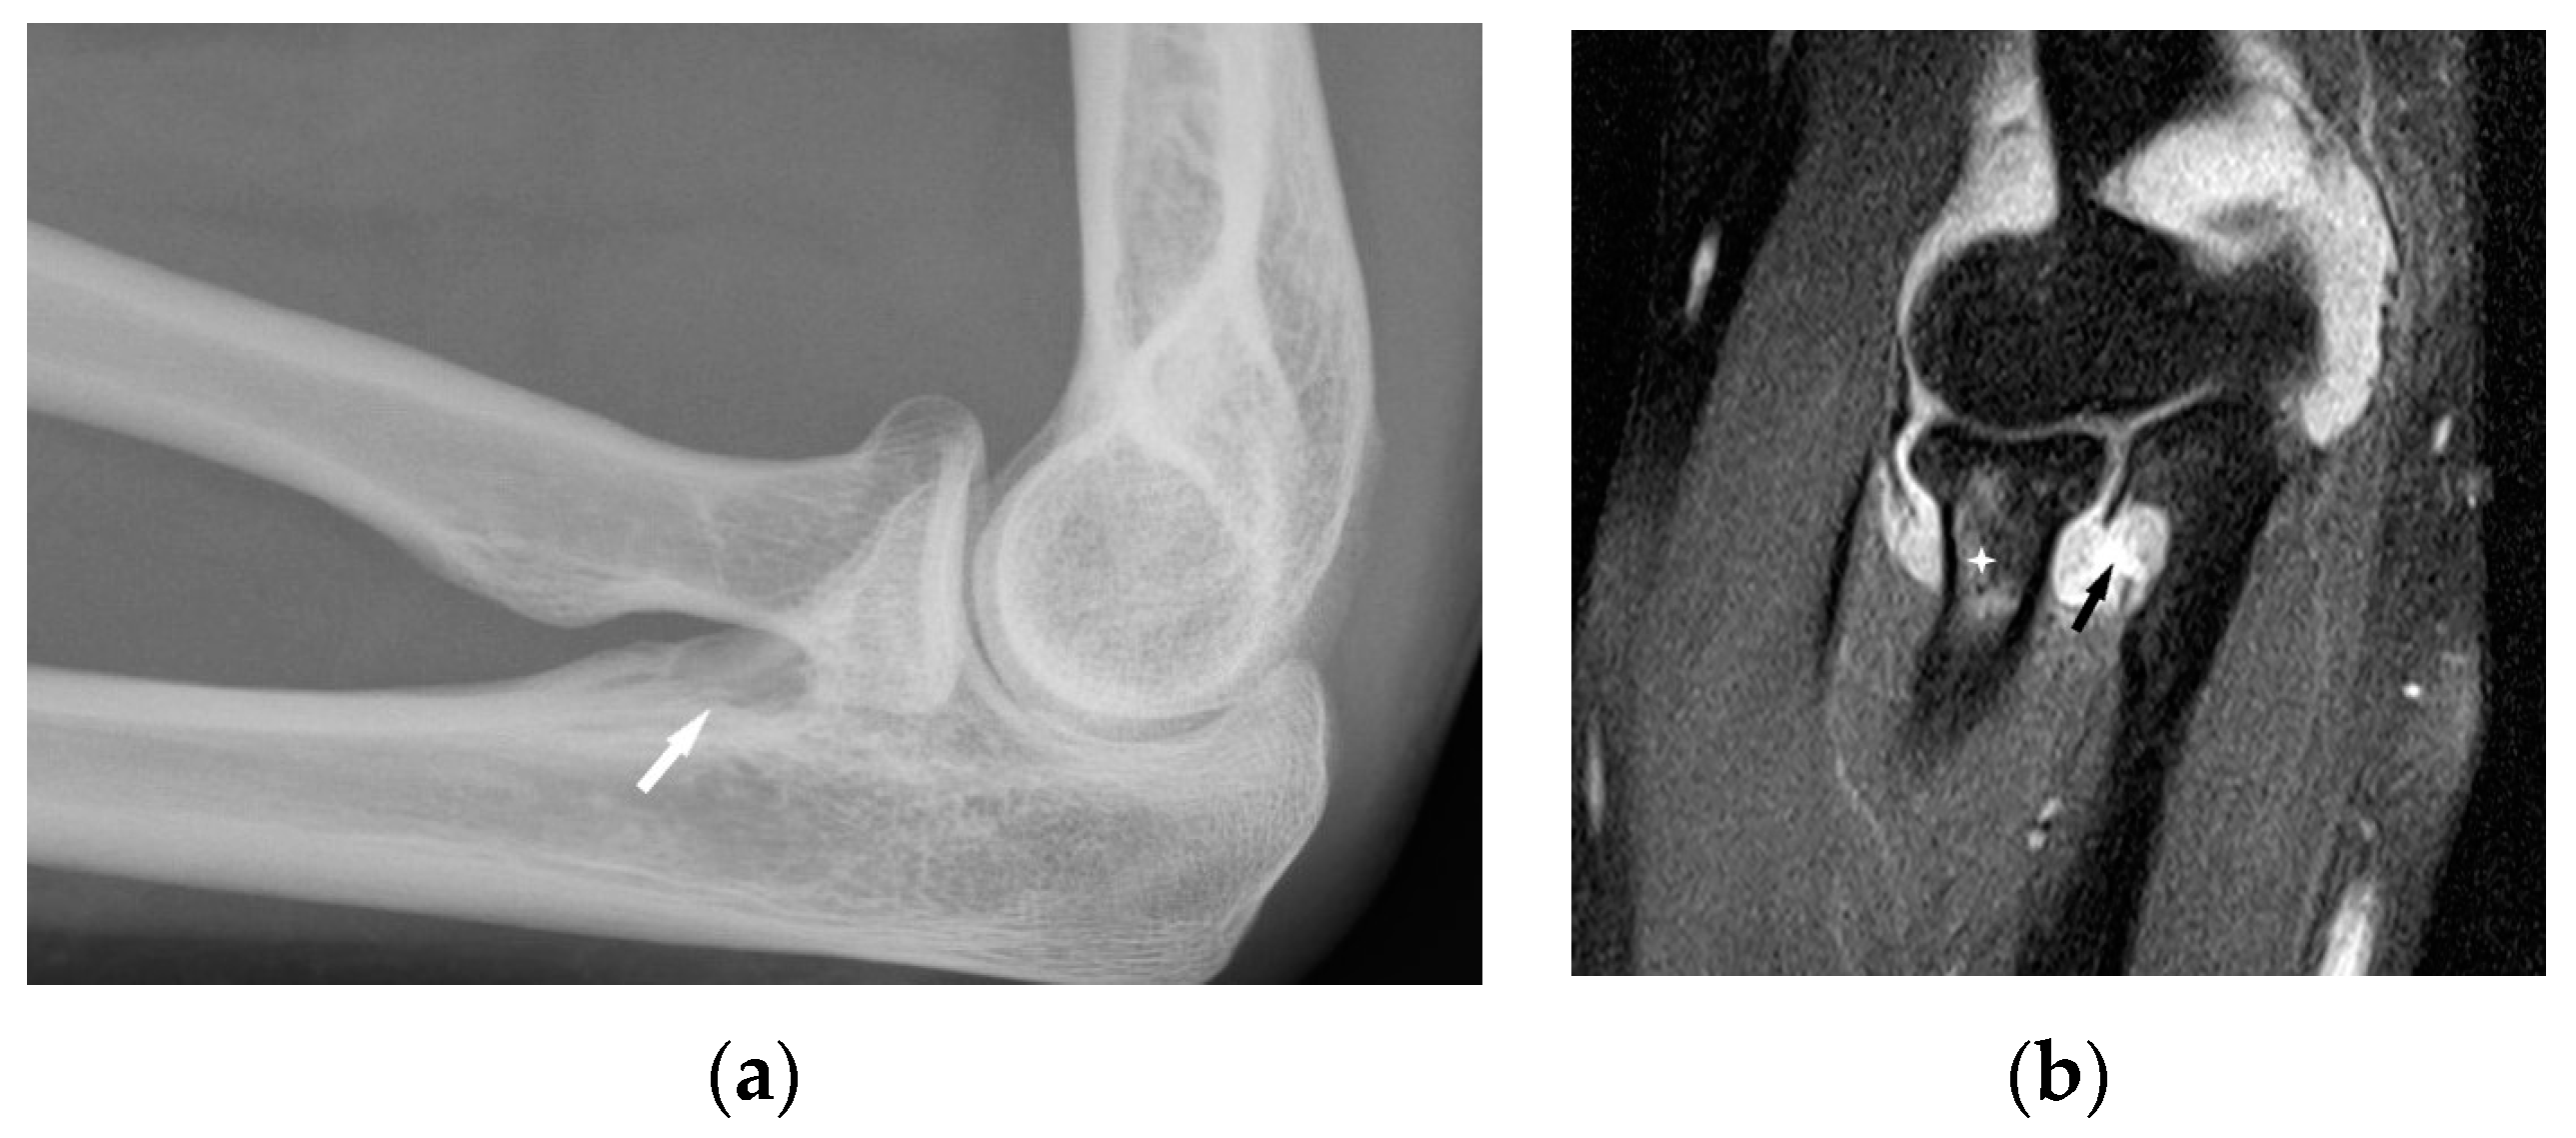

Chronic arthritis, either mono-articular or poly-articular, occurs in the later phases of the disease, usually as a part of a multisystem manifestation. In addition to synovitis (Figure 5a,b), erosions of the articular surfaces may be present, making it necessary to differentiate the lesions from reactive or rheumatoid arthritis [19]. An additional difficulty is that the rheumatoid factor may be positive in 10–47% of cases [20]. If differential diagnosis is necessary, a synovial US-guided biopsy is performed. Detection of granulomas in a synovial biopsy sample helps make the diagnosis of sarcoidosis [20]. X-ray shows soft tissue swelling and epiphyseal demineralization.

Long-lasting joint inflammation leads to the narrowing of the joint space. In the sarcoid arthritis diagnostic imaging, we mainly use X-ray, US, and MR imaging. MRI shows with high sensitivity the joint effusion and features of synovitis, cartilage destruction, and inflammatory changes of periarticular structures such as peritendinitis, tendinitis or bursitis (Figure 5a,b) [20].

Figure 5. Radiograph (a) and MRI of the elbow (b) performed in a 45-year-old woman with sarcoidosis. Osteolytic lesion in the proximal part of the elbow bone ((a), white arrow). T2-weighted image with fat saturation revealed a synovitis, erosion in the proximal part of the elbow bone corresponding to this bone lesion (black arrow) and slight bone marrow edema in the head and neck of the radius (asterisk).